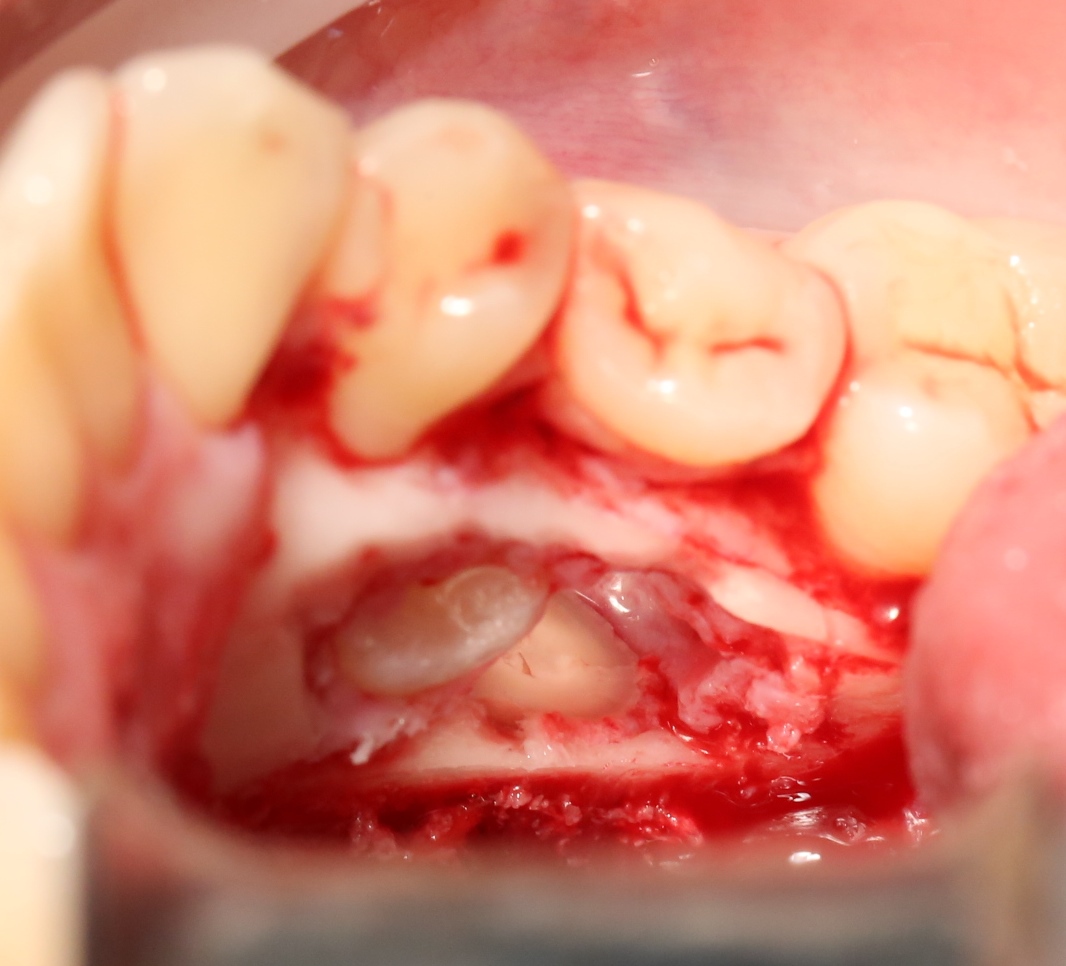

В данном случае я использовал обычную коллагеновую губку — и то, только для того, чтобы «костная дверца», которую я выпилил в самом начале операции, не провалилась внутрь:

Теперь запиливаем «костную дверцу» на ее законное место:

И накладываем швы.